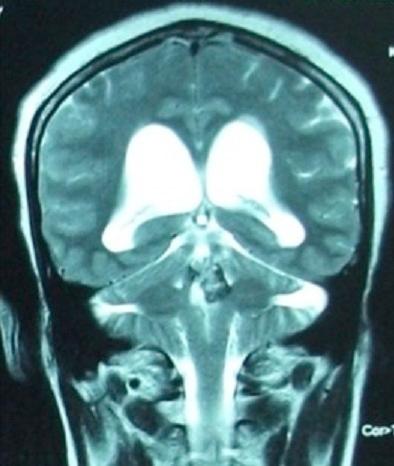

[Cavernoma of the fourth ventricle: report of a case and review of the literature].

[Cavernoma of the fourth ventricle: report of a case and review of the literature].[第四脑室海绵状血管瘤:一例报告并文献复习]